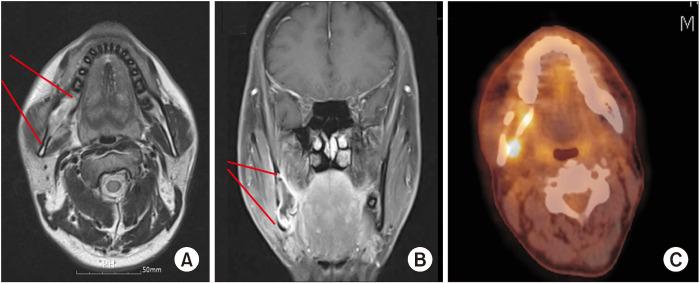

Primary intraosseous squamous cell carcinoma (PIOSCC) is very rare type of squamous cell carcinoma (SCC) that occurs within the jaw and arises from remnants of odontogenic epithelium with no connection to the oral mucosa. This study reports two cases of PIOSCC of the mandible. Reported in this article are two cases of PIOSCC of the mandible that were treated with resection and reconstruction using a fibular free flap. The first case was a 36-year-old male patient who complained of right mandibular pain. Computed tomography (CT) and panoramic radiograph revealed a large radiolucency in the mandibular ramus area. At first, an odontogenic keratocyst was tentatively diagnosed, and an excision procedure was carried out at another clinic. A final biopsy after cyst enucleation revealed well-differentiated SCC, so we proceeded with segmental mandibulectomy and reconstruction using a fibular free flap. The second case was a 48-year-old male patient with left mandibular pain. CT and panoramic radiograph revealed irregular radiolucency in the mandibular angle area near tooth #38. At first, osteomyelitis was tentatively diagnosed, and a curettage was carried out. A later biopsy revealed well-differentiated SCC, so segmental mandibulectomy and reconstruction with a fibular free flap were secondarily performed. Our two cases have had no recurrence. The facial appearance of both patients is satisfactory, and the neo-mandibular body created using a fibular bone transfer displays adequate bony volume.

原发性骨内鳞状细胞癌(PIOSCC)是一种非常罕见的鳞状细胞癌(SCC),发生于颌骨内,起源于牙源性上皮残余,与口腔黏膜无连接。本研究报告了两例下颌骨PIOSCC病例。本文报道了两例下颌骨PIOSCC病例,采用游离腓骨瓣进行切除和重建治疗。第一例是一名36岁男性患者,主诉右下颌疼痛。计算机断层扫描(CT)和全景X线片显示下颌支区域有一个大的透射区。起初,初步诊断为牙源性角化囊肿,并在另一家诊所进行了切除手术。囊肿摘除后的最终活检显示为高分化SCC,因此我们进行了下颌骨节段性切除并用游离腓骨瓣进行重建。第二例是一名48岁男性患者,有左下颌疼痛。CT和全景X线片显示38号牙附近下颌角区域有不规则透射区。起初,初步诊断为骨髓炎,并进行了刮除术。后来的活检显示为高分化SCC,因此二期进行了下颌骨节段性切除并用游离腓骨瓣进行重建。我们的两例病例均无复发。两名患者的面部外观均令人满意,使用腓骨骨移植构建的新下颌体显示出足够的骨量。